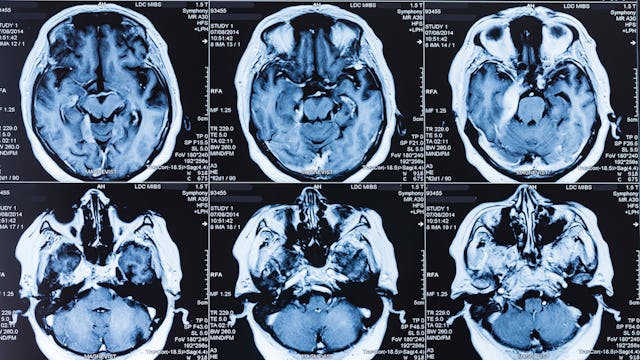

According to the Seattle Times, the woman was admitted to a local hospital earlier this year after suffering a seizure. After doctors examined her brain tissue, they determined she was infected with Balamuthia mandrillaris, an amoeba found in soil and fresh water — and it had been eating her brain for almost a year.

“When I operated on this lady, a section of her brain about the size of a golf ball was bloody mush,” Dr. Charles Cobbs, a neurosurgeon at Swedish, tells the Times. “There were these amoeba all over the place just eating brain cells. We didn’t have any clue what was going on, but when we got the actual tissue we could see it was the amoeba.”